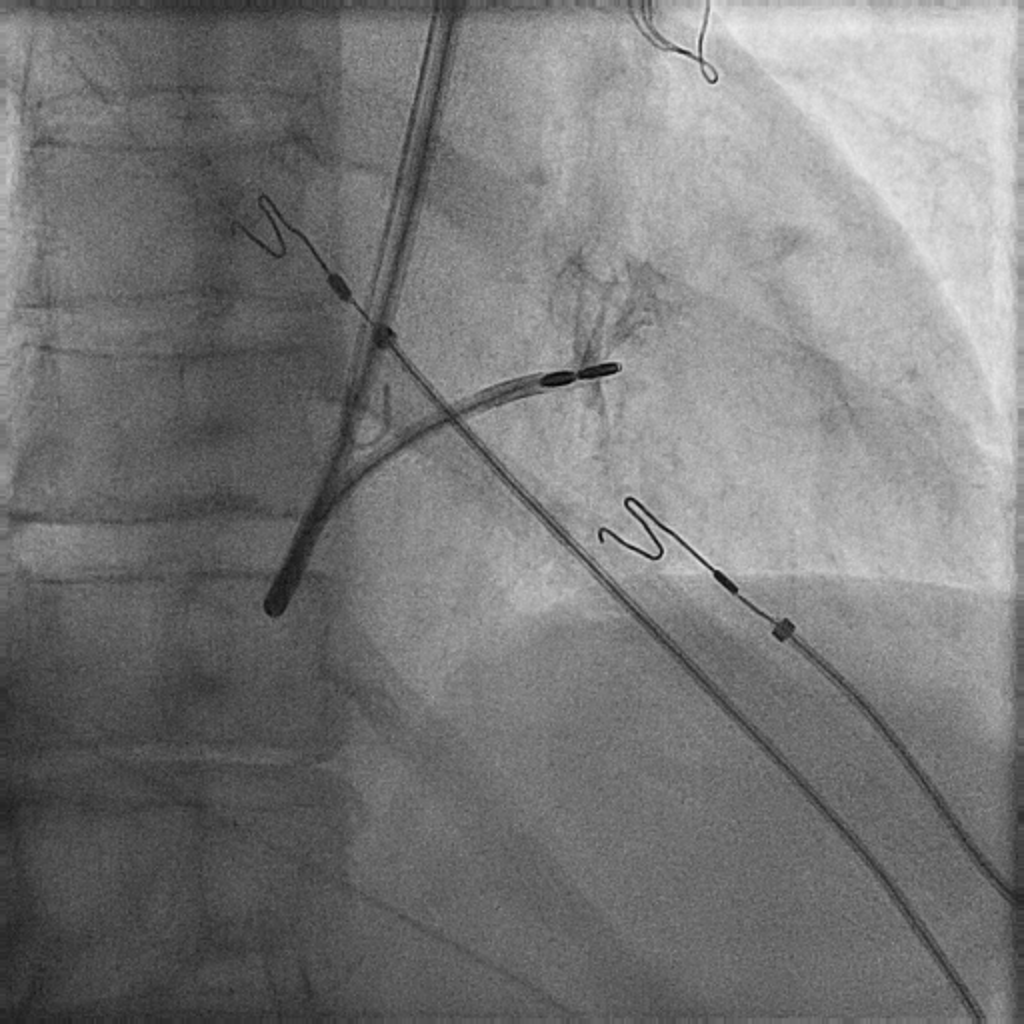

Stop sleeping on @biotronik Selectra 3D. This is amazing for getting leads into the RV in patients with persistent left SVC. Here we placed a left bundle pacing lead without much difficulty.